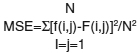

MSE

Mean square error (MSE) is given by:

Where, f is the original image F is the filtered image and N is the size of image. MSE is an estimator in many ways to quantify the amount by which a filtered/noisy image differs from noiseless image